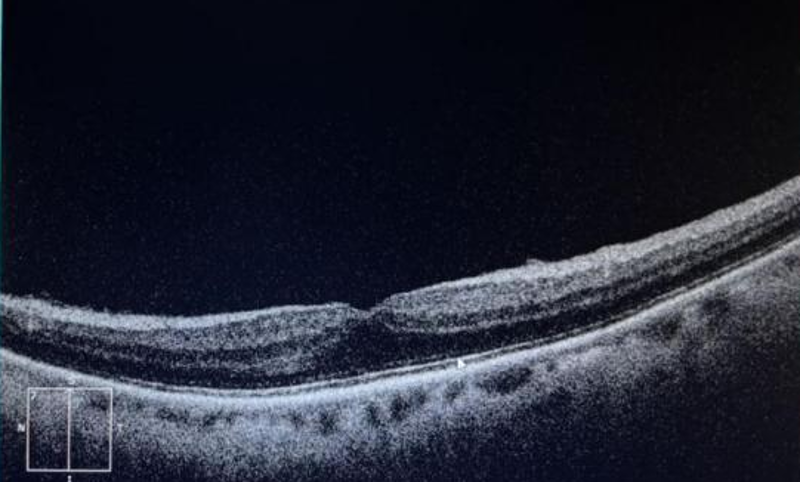

术前左眼黄斑OCT:左眼黄斑区可见条状高反射——黄斑前膜